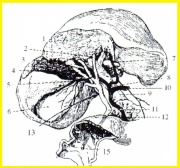

| 11:17, 27 במאי 2013 | Gallbladder14.jpg (קובץ) |  |

36 קילו־בייטים | Zvi kaufman | 2 | |

| 11:15, 27 במאי 2013 | Gallbladder6.jpg (קובץ) |  |

56 קילו־בייטים | Zvi kaufman | 2 | |

| 11:10, 27 במאי 2013 | Gallbladder5.jpg (קובץ) |  |

61 קילו־בייטים | Zvi kaufman | 4 | |

| 11:02, 27 במאי 2013 | Gallbladder4.jpg (קובץ) |  |

33 קילו־בייטים | Zvi kaufman | 2 | |

| 11:00, 27 במאי 2013 | Gallbladder3.jpg (קובץ) |  |

62 קילו־בייטים | Zvi kaufman | 2 | |

| 10:59, 27 במאי 2013 | Gallbladder2.jpg (קובץ) |  |

176 קילו־בייטים | Zvi kaufman | 2 | |

| 10:57, 27 במאי 2013 | Gallbladder1.jpg (קובץ) |  |

43 קילו־בייטים | Zvi kaufman | 2 | |

| 04:13, 23 במאי 2013 | Gallbladder13.jpg (קובץ) |  |

29 קילו־בייטים | Zvi kaufman | שוחזר לגרסה מ־04:11, 23 במאי 2013 | 5 |